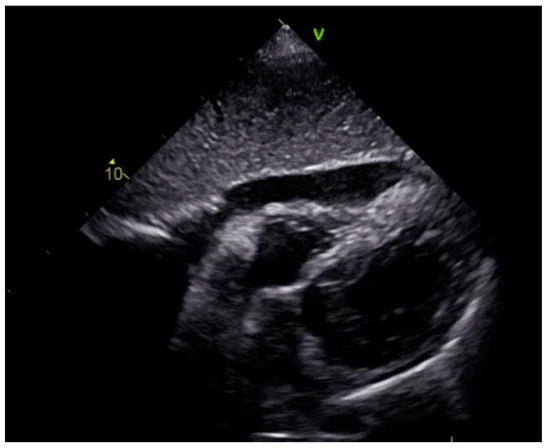

As a result, the patient was referred to a specialized medical institution. Upon admission, the patient was conscious, confused, hypotensive (TA 80/50 mmHg), with a heart rate of about 110/min, and showing clinical signs of hypoperfusion and cardiogenic shock, Killip IV. The medical staff administered sedation, inserted an endotracheal tube, and placed her on invasive mechanical ventilation. The patient was given crystalline solutions, inotrope, and vasopressor medication. An urgent echocardiographic examination was performed due to a rough systolic murmur over the precordium. It revealed akinesia of all medioapical segments of the left ventricle and akinesia basally inferior, where the myocardium was fibrously altered. Other hyperkinetic basal segments formed a dynamic obstruction of the left ventricular outflow tract (LVOTO) with turbulent flow and moderate mitral regurgitation (Figure 2 and Figure 3). The maximum gradient above the LVOT was 160 mmHg (Figure 4). The aortic valve area was 1.8 cm2 (Figure 5). The ejection fraction of the left ventricle (LVEF) was estimated to be 25%. The examination also revealed pericardial effusion with separation between pericardial layers along the right ventricle and atrium of up to 1.2 cm, but without any signs of tamponade.

Figure 2.

Echocardiography registered basal hyperkinetic segments of the left ventricle and formed a dynamic obstruction of the left ventricular outflow tract (a—LVOT, b—cuspi anterioris valvulae mitralis, c—aortic valve).

Figure 3.

Echocardiography registered moderate mitral regurgitation (d—LVOT, e—mitral regurgitation).